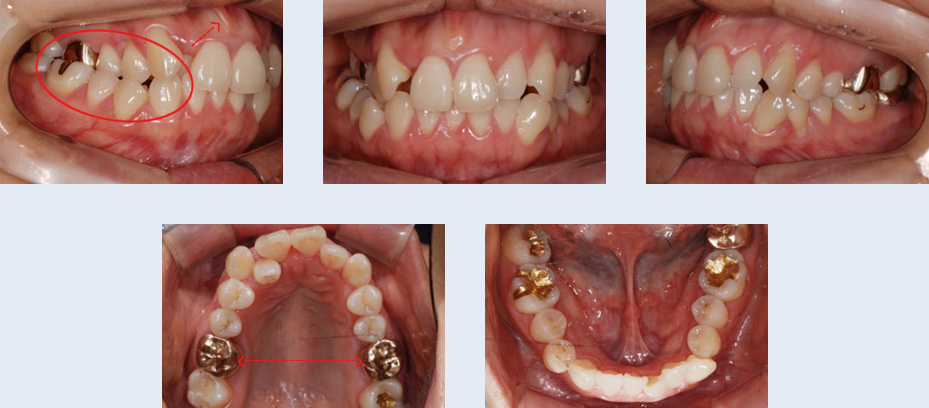

2년 전 식립한 임플란트의 보철물이 탈락된 상태로 1년간 지내오신 25세 여성입니다. 임플란트 식립을 위해

사용한 인공 뿌리를 제거하고 치아가 가지런해 지길 원하셨습니다. 자연치아로만 치료를 진행할 수 있도록 하기

위해 인공 뿌리를 제거하고, 빈 공간으로 치아를 이동시켰습니다.

임플란트 제거 후 생긴 빈 공간으로 브라켓을 부착한 사랑니를 이동시켜 추가적인 임플란트 식립이나 보철 치료

없이도 자연스러운 치열을 갖게 되었습니다.